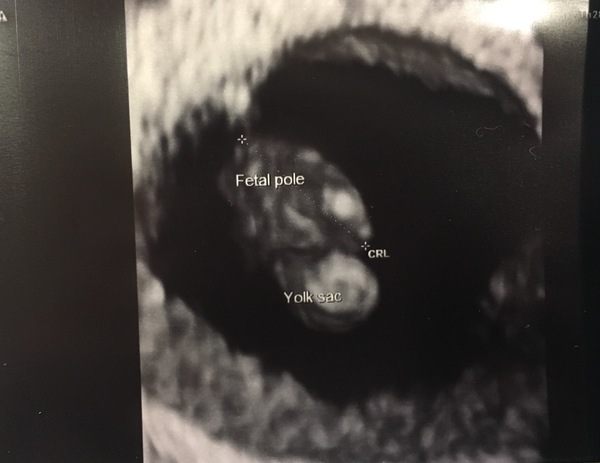

Here is my scan from last Thursday (6+6). All looking good with crown rump length of 9.5mm and heartbeat seen. Still very anxious though tbh.